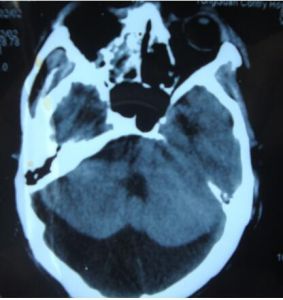

枕大池(又稱小腦延髓池),位於顱後窩的後下部,小腦下面、延髓背側面與枕鱗下部三者之間。 向前經小腦溪通第四腦室;向前外經延髓側面通延髓池。三維斷面均可顯示。